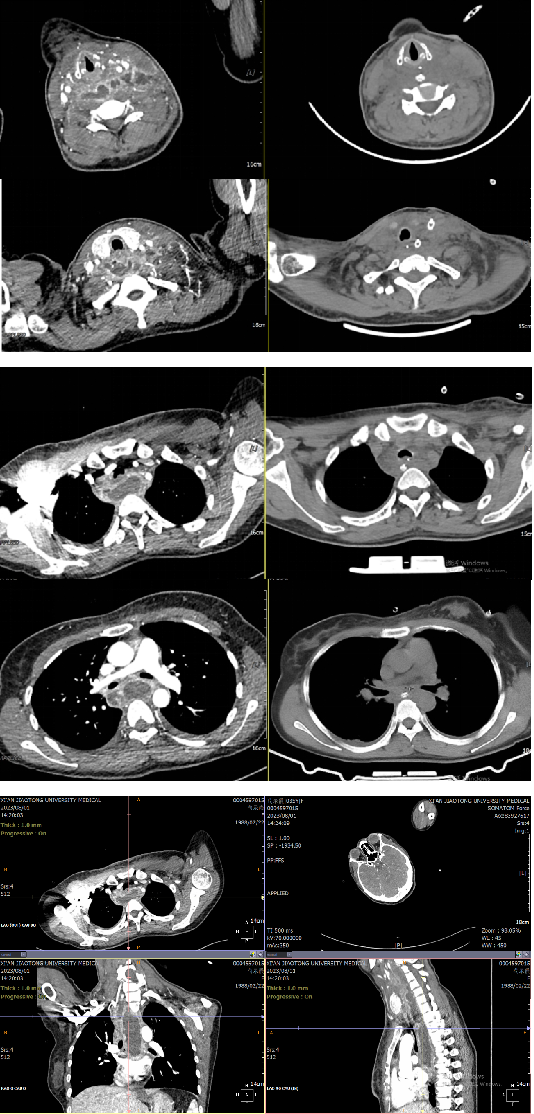

胸外科李少民主任评估患者病情后与家属沟通:“患者目前诊断为纵脓肿,已出现感染性休克表现,病情危重,药物保守治疗好转机会渺茫,需进行手术探查,但手术风险极大;但我们一定会尽最大努力为患者争取一线生机。”家属同意手术治疗。在准备急诊手术的过程中,同时给予抗休克治疗,并急诊完成了胃镜、电子支气管镜、增强CT等检查;评估患者纵隔脓肿是否由食管或气管损伤引起,进一步明确脓肿与周围组织及血管的解剖关系。术前准备完善后,第一时间接入急诊手术间进行手术。因脓肿波及颈部、胸部,且颈部肿胀严重、气管受压,全麻气管插管也是一个挑战;幸运的是由经验丰富的麻醉医师张鹏顺利完成了气管插管。此时面临更大的挑战:手术入路的选择是颈部入路还是胸部入路?能否通过一个入路解决问题?李少民主任通过详细阅读术前检查以及丰富的临床经验选择行颈部左侧切开,于胸锁乳突肌深面暴露脓肿,探查脓肿位于椎前间隙,上达会厌后方,下至后纵隔气管分叉,有大量黄色浑浊脓液积存,吸出脓液,量约150ml;过氧化氢液冲洗,于颈部切口沿椎前间隙留置负压引流管两根,上管至会厌上方,下管至气管分叉水平,引流满意。术后给予抗感染及支持疗法,术后第1天患者颈部肿胀明显好转,呼吸困难及声音嘶哑明显好转,体温正常。患者清楚的向医生说出“谢谢您们把我从鬼门关拉了回来。”